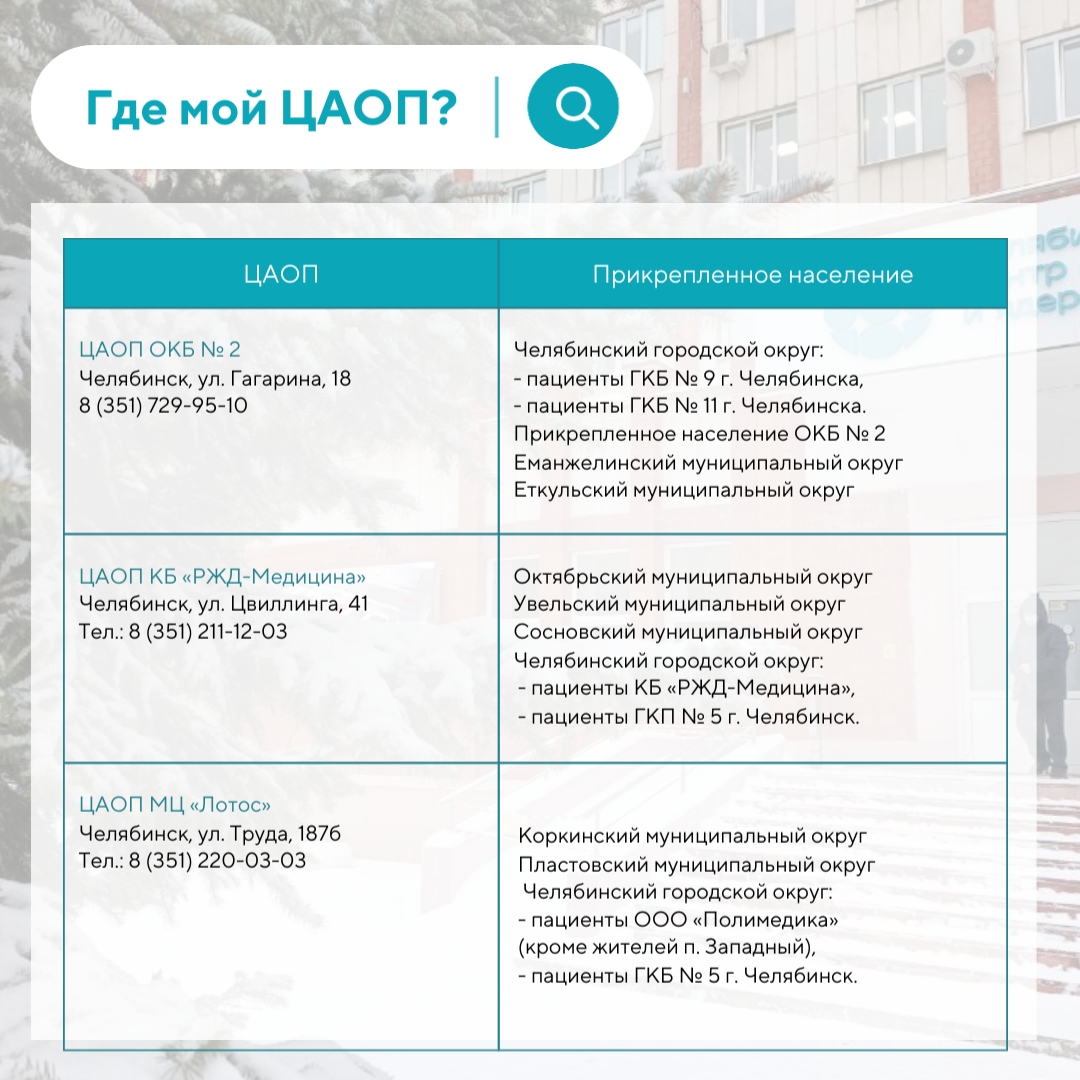

В Челябинской области пациенты прикреплены к конкретным Центрам амбулаторной онкологической помощи, а найти свой можно в карточках:

В Челябинской области пациенты прикреплены к конкретным Центрам амбулаторной онкологической помощи, а найти свой можно в карточках:

Инфографика предоставлена пресс-службой ЧОКЦОиЯМ

Инфографика предоставлена пресс-службой ЧОКЦОиЯМ